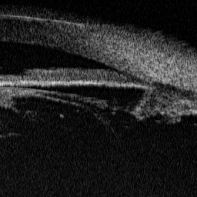

Из-за выраженных изменений строения переднего

сегмента глаз не удалось провести измерения всех параметров у 9 пациентов с первичной

глаукомой и у 5 - со вторичной глаукомой. В качестве примера приводим УБМ

больного Ч. с первичной закрытоугольной глаукомой (рис. 3) и больного К. с

оперированной закрытоугольной глаукомой (рис. 4).

а) б)

Рис. 3 - УБМ переднего отрезка глаза больного

Ч.: а) на 6 час., б) на 12 час